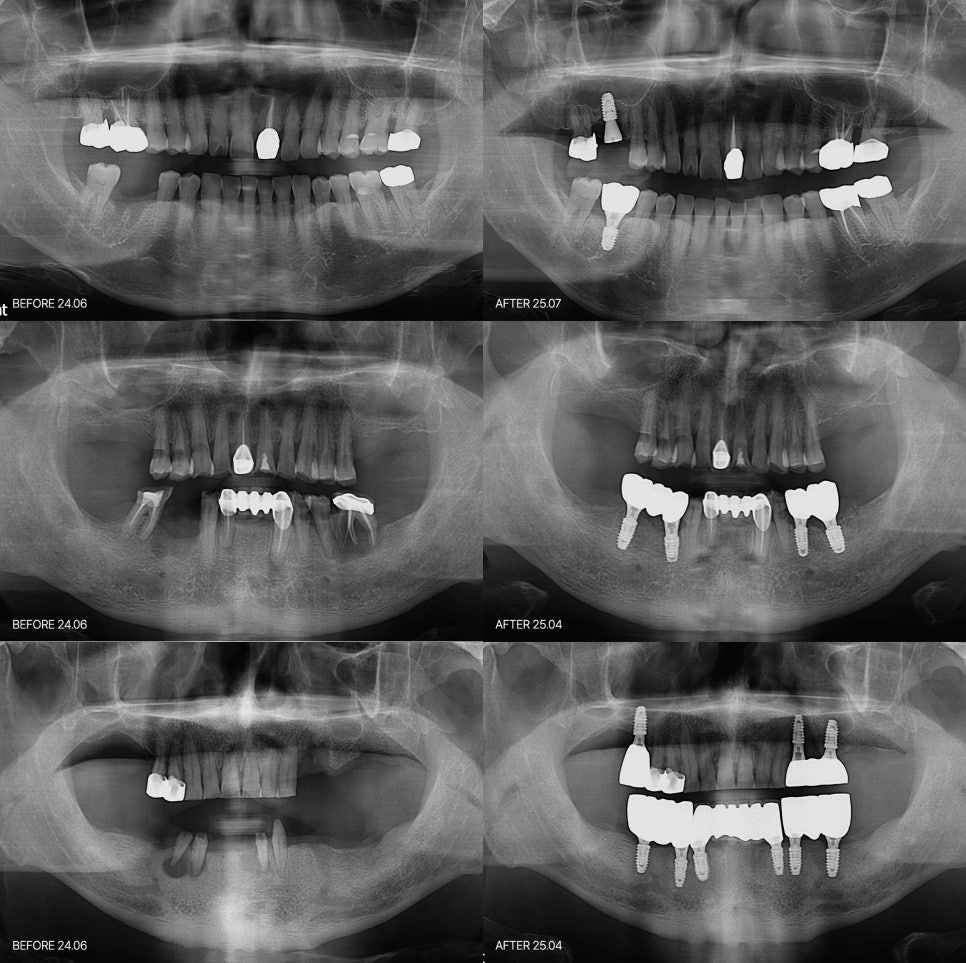

재수술 상담에서 다시 진단을 했을때

발견이 되는 부분중에 많은 케이스는

뼈가 충분하지 않은 경우

임플란트의 간격이 너무 가깝게 식립되어

시간이 지나면서 뼈가 흡수된 경우

잇몸뼈보다 너무 얕게 임플란트가 심어진 경우

씹는데 힘이 강한데 교합 조정이 부족했던 경우